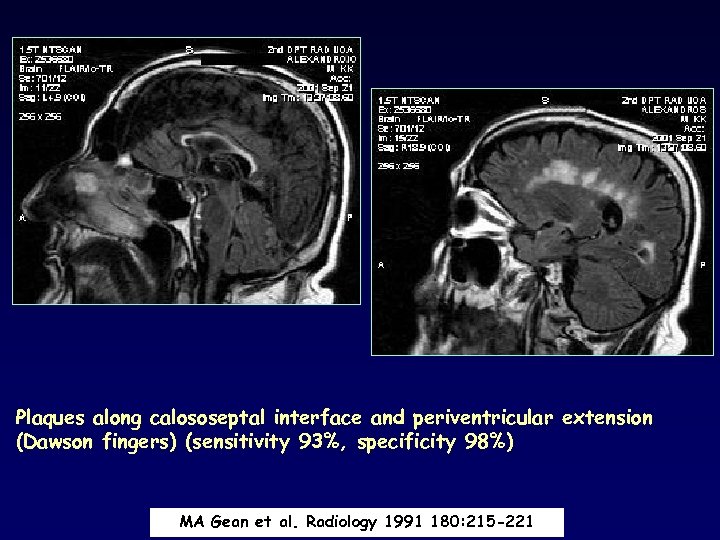

Plaques along calososeptal interface and periventricular extension (Dawson fingers) (sensitivity 93%, specificity 98%) MA Gean et al. Radiology 1991 180: 215 -221